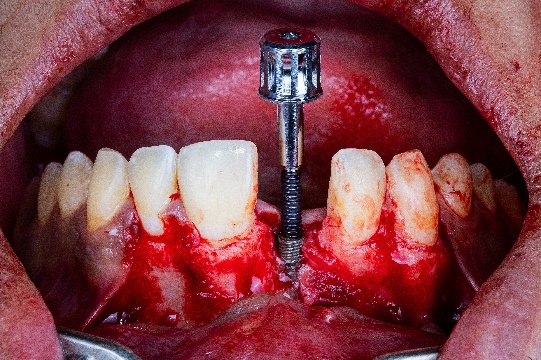

После установки имплантата доктор ввел костный материал и накрыл его нерассасывающейся мембраной из политетрафтороэтилена (ПТФЭ), усиленной титановым каркасом. Такая мембрана предотвращает врастание в нее мягких тканей. Края мембраны были закреплены титановыми пинами (рис. 11, 12).

Рис. 11, Рис. 12: Операция по направленному наращиванию костной ткани.